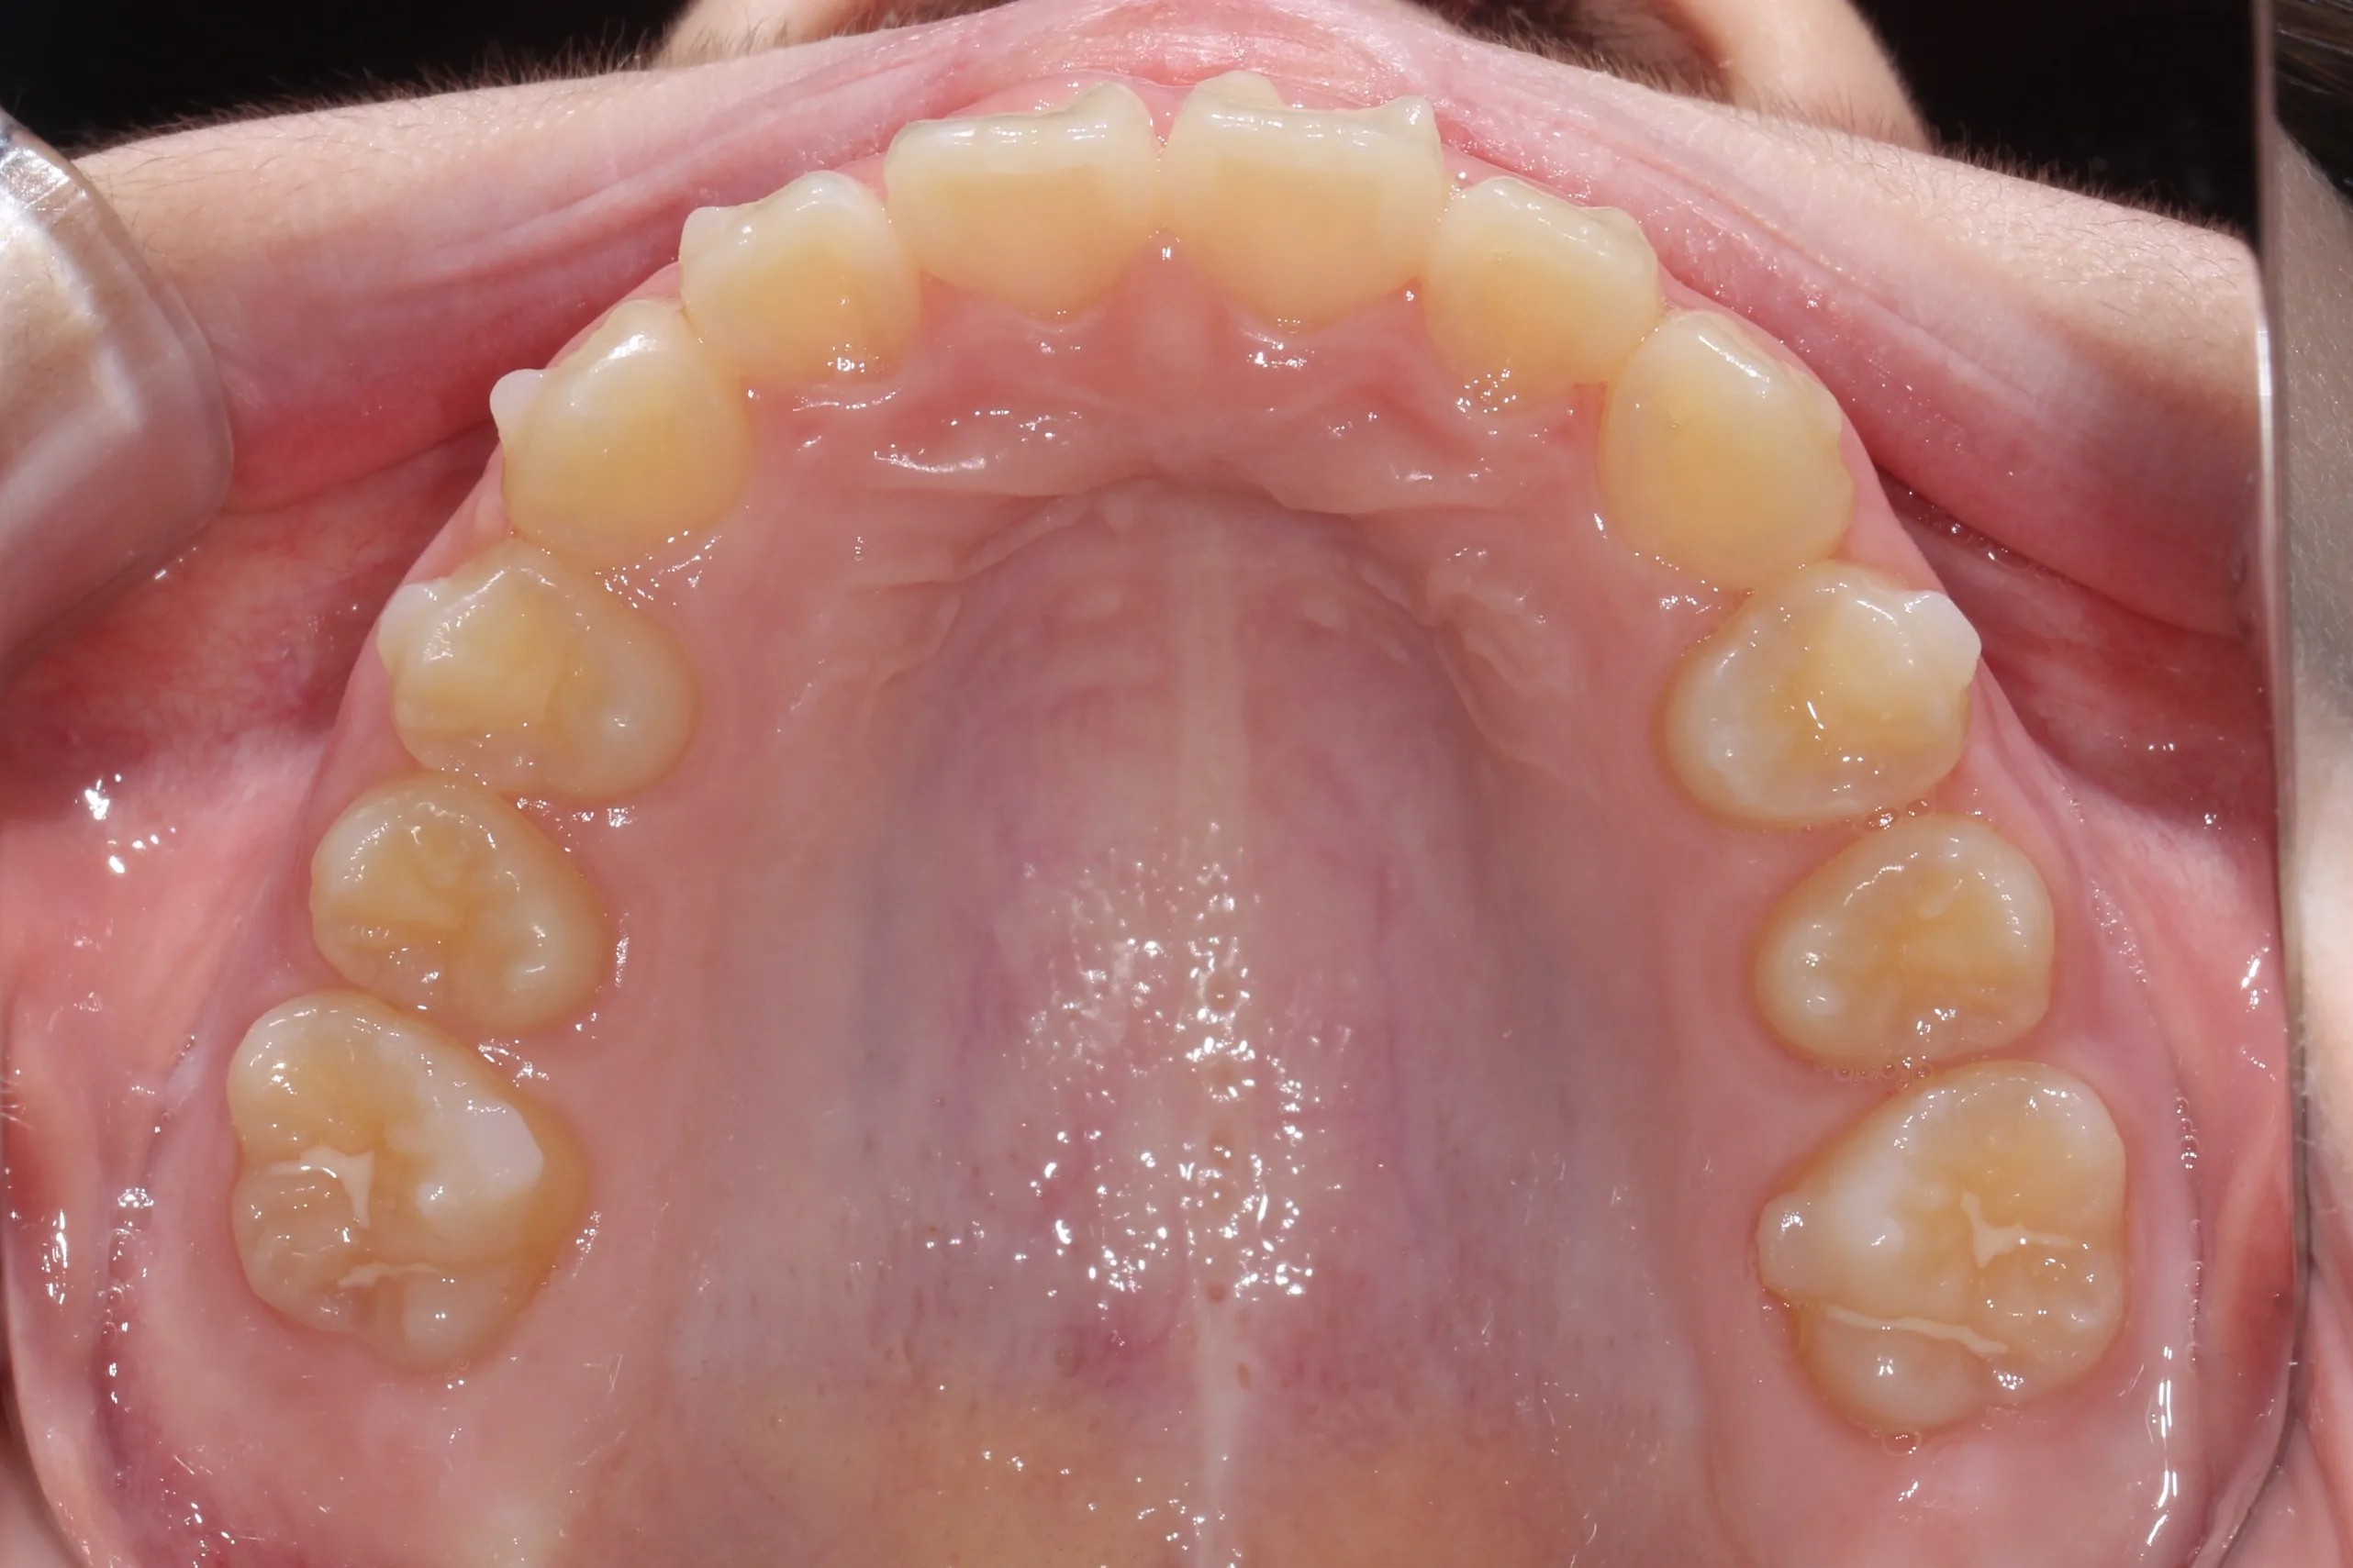

만 11세 환자분께서 튀어나온 앞니와 다물어지지 않는 입술 때문에 내원하셨습니다. 검진 결과 상악 전돌을 동반한 2급 부정교합(Class II malocclusion) 상태였으며, 아래턱의 성장이 다소 부족하여 골격적인 조화가 필요한 상황이었습니다.

이번 치료에는 인비절라인 퍼스트(Invisalign First)에 하악 전방 견인(Mandibular Advancement, MA wing)을 추가하여 치료를 진행하였습니다. 성장기라는 시기적 특성을 적극 활용하여 아래턱의 점진적인 성장을 유도하고, 과도한 상악 전치부 돌출을 개선하는 데 치료의 핵심 전략을 두었습니다.

2년 7개월의 치료 과정을 거치며 환자분의 협조도 덕분에 안모 프로파일과 교합이 안정적으로 개선되었습니다. 성장기라고 해서 무조건 교정이 어려운 것은 아닙니다. 적절한 시기에 맞춤형 장치를 선택한다면 골격적 불균형을 효과적으로 바로잡을 수 있습니다.